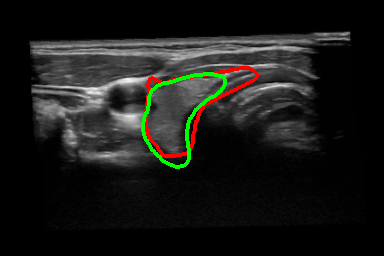

Thyroid Segmentation: The thyroid data used in this experiment has been acquired from a publicly available dataset [3] which includes freehand acquired thyroid US volumes from healthy human subjects imaged with a MHz probe. The proposed approach is compared with four different algorithms which has been reported by Narayan et. al. [1], (Table. 2). The only limitation in trying to compare commonality is that the dataset used for this comparison is not the same as the dataset used in prior art [1]. 2D visualization of segmentation is shown in Fig. 3(k) - (n) and the thyroid segmentation in the whole volume is visualized 11footnotemark: 1. Table 2 shows that our proposed frame work obtain better results than the prior art.